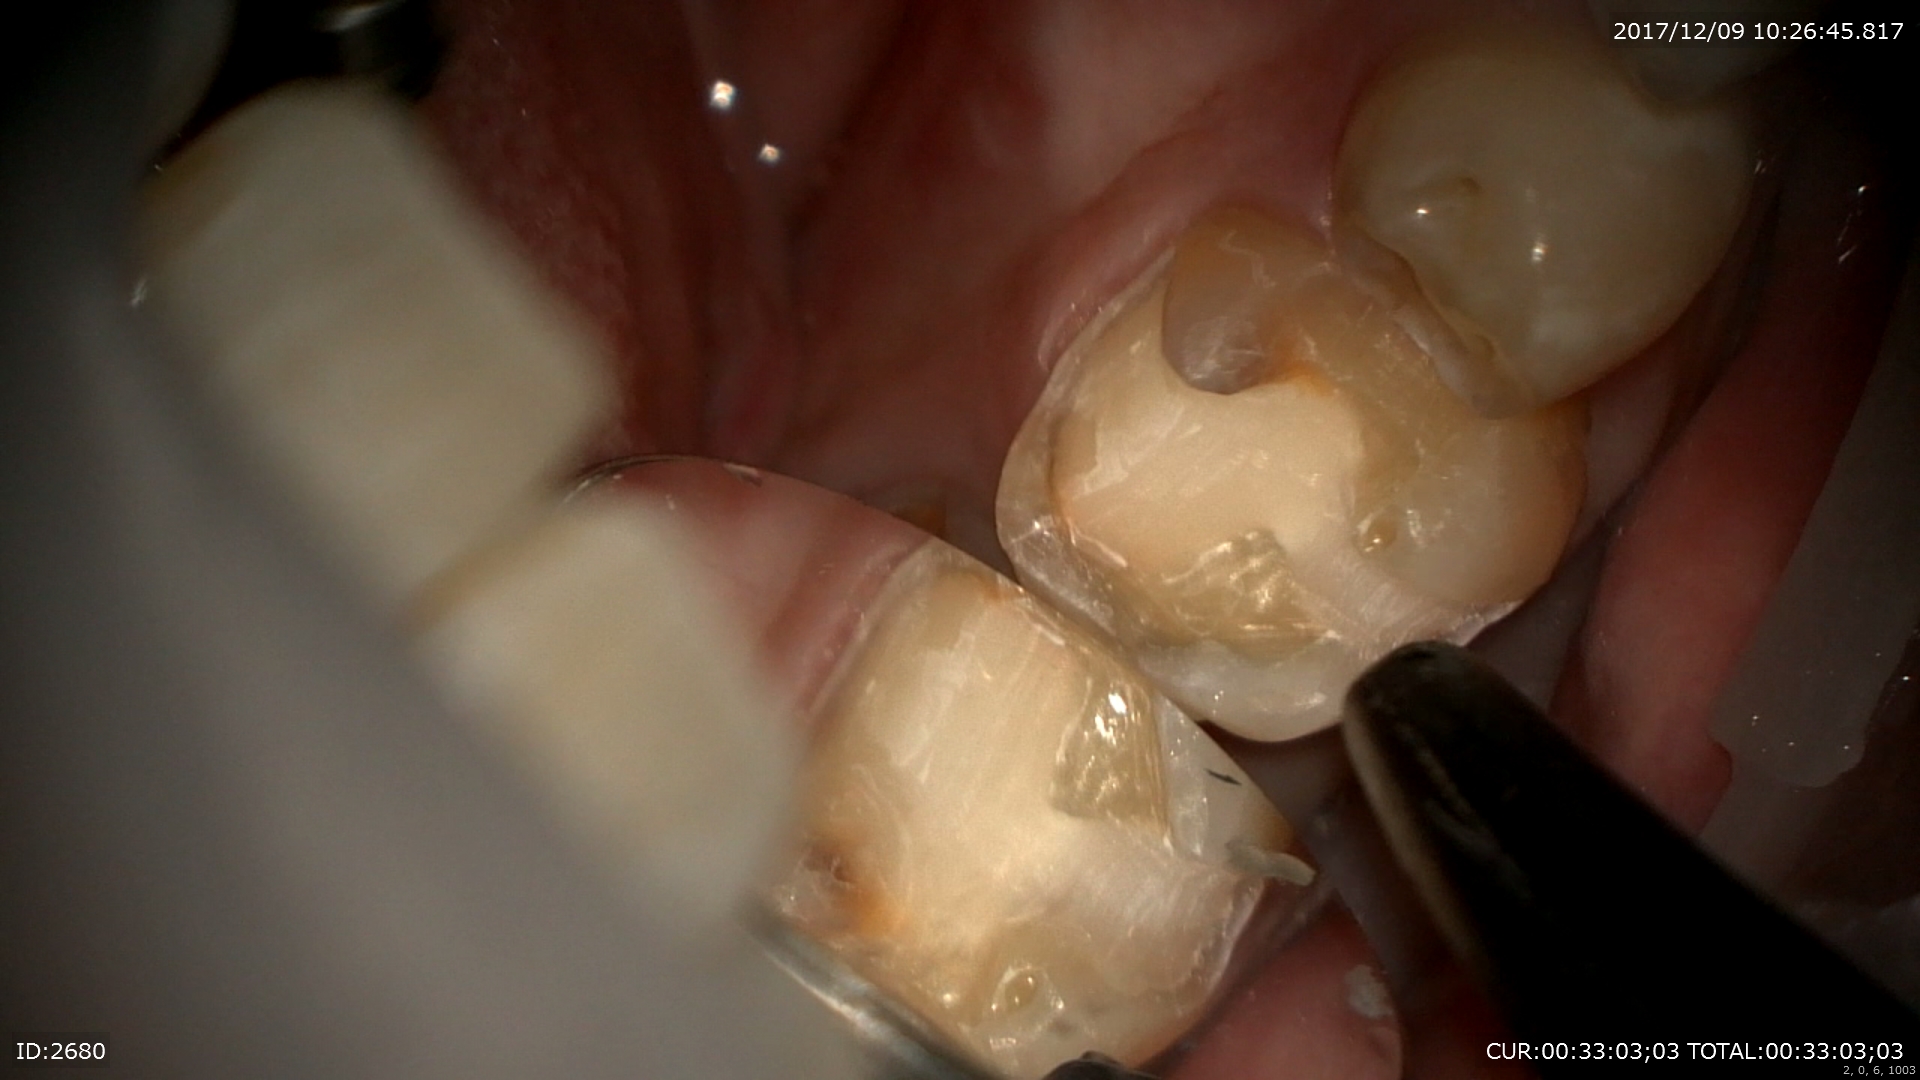

次は虫歯のケース。プラスチックはこのように汚れ(細菌)を寄せ付け二次虫歯を発生させます。

外すと あらま。感染だらけ。マイクロスコープで丁寧に無痛で。

感染を取るとこんなに歯がなくなってしまいます。裸眼でとったら神経見えるかも。。

MTAで神経保護

また神経に優しい治療ができて幸せ!